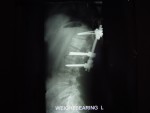

He has TWO rods in his back for support up and down... Two screws at the bottom of each rod and one at the top... He is in recovery at this time more than likely still...

He Faces a LONG three to Four months of bed rest while his back heals up... The Best of luck in all of this. The Doctors were able to do ALL of the surgery through his THIN little body Via his BACK and Did not have to cut his chest etc at all... He has 2 rods in his back and that is NOW confirmed and what I posted last night late is all good...

The hardware is coming out! On April 28th I'm gettin' this monkey off (out of) my back. Hopefully it is the source of the leg pain that has slowed the recovery process.

- The Monkey: Side View